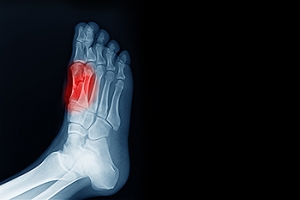

In many cases the cause of toe pain is obvious, but in others, a podiatrist may want to use more advanced methods to determine the problem. These can range from simple visual inspections and sensation tests to X-rays and MRI scans. Prior medical history, family medical history, and any recent physical traumatic events will all be taken into consideration for a proper diagnosis.

Toe pain can originate from corns, calluses, hammertoes, and bunions, as well as ingrown toenails, sprains, fractures, and dislocations. Corns develop as the toe rubs against the inside of a shoe which causes the skin to thicken as a form of protection. A corn is typically cone-shaped and has a small, hardened spot that points inward. When a corn is pressed into the skin, the toe becomes painful. Corns usually form on the top or side of the toe. A callus is also a thickened patch of skin that generally forms on the bottom of the foot. Calluses are the result of friction from the toe rubbing against the inside of a shoe. They may also occur by walking barefoot or having flat feet. A hammertoe is a bump on the knuckle of the second toe that is produced by wearing shoes that are too short for your feet. The bony protrusion rubs against the top of the shoe causing pain and irritation. A bunion is a malformation of the big toe. The base of the big toe pushes away from the smaller toes, forcing the top of the big toe to press toward the other toes. Bunions can be hereditary, or they can result from injury to the toe joint or from wearing high heels with a narrow toe box. The toe becomes inflamed, and a bump may develop at the end of the misplaced bone. Ingrown toenails typically affect the big toe and its surrounding skin. The nail will dig into the skin and become painful. Wearing tight or narrow shoes that compress the big toe causes the nail to grow into the fleshy part of the toe. Cutting toenails incorrectly can also add to the development of an ingrown toenail. A toe sprain originates from a torn or stretched ligament. Strapping the injured toe to the toe next to it for stabilization is common. A broken or fractured toe usually occurs from trauma like dropping a heavy object on it or bumping into something extremely hard and rigid. Osteoporosis, a thinning of the bones, can also bring about toe fractures.